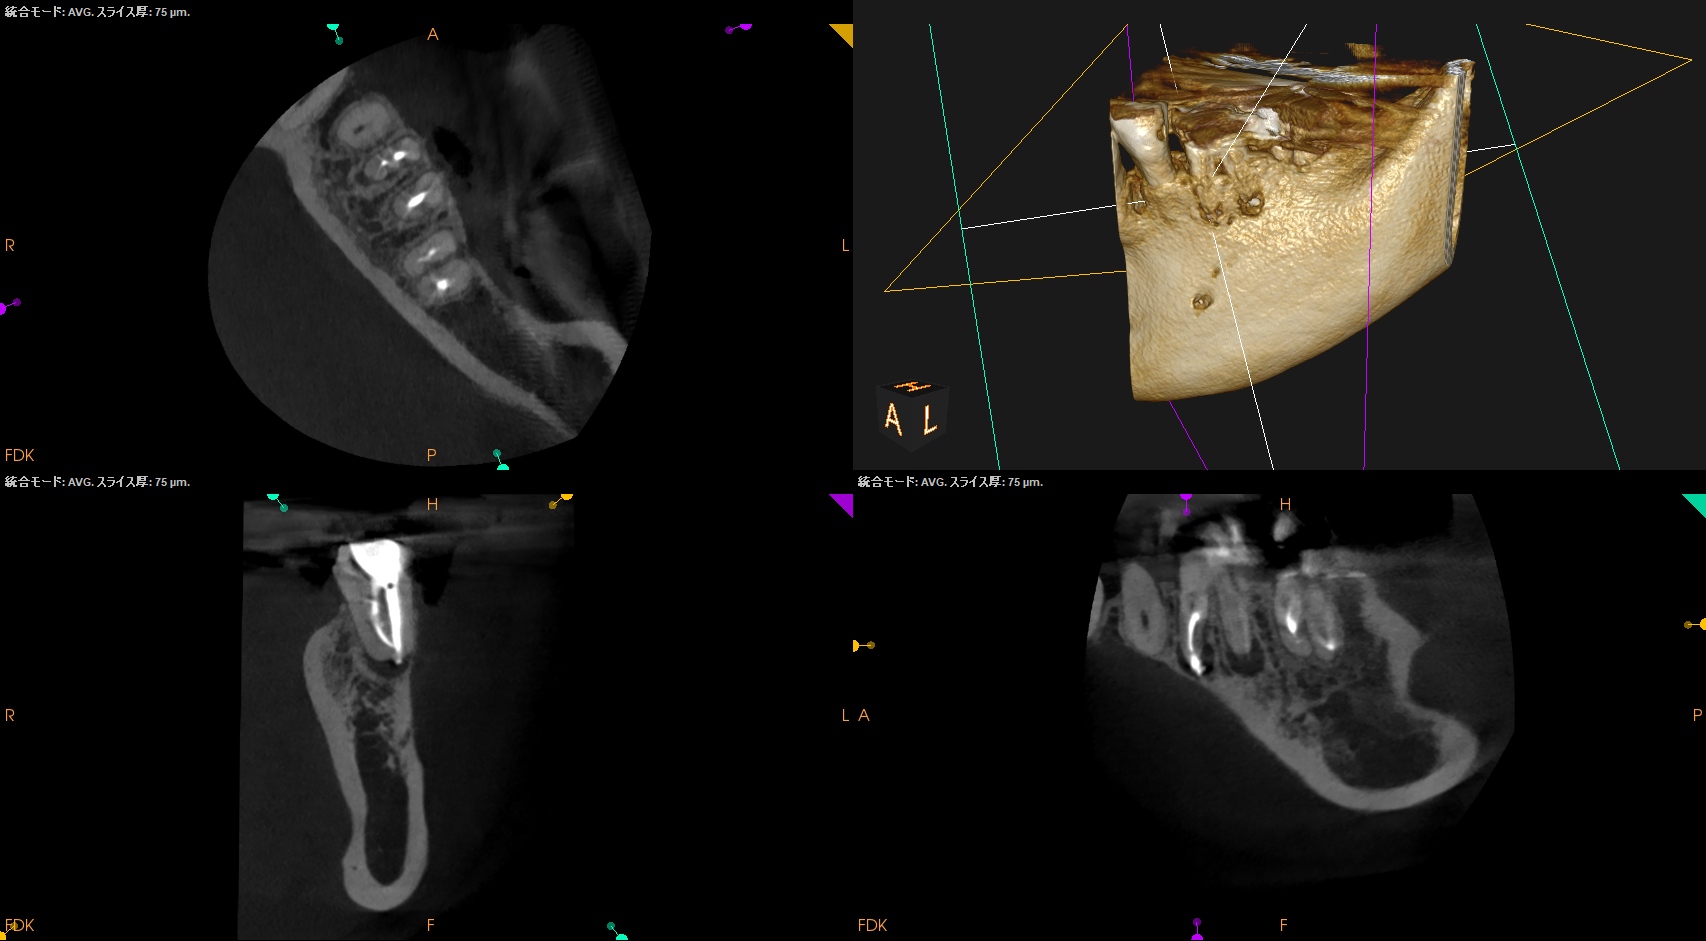

術後にPA, CBCTを撮影した。

MB

ML

D

B